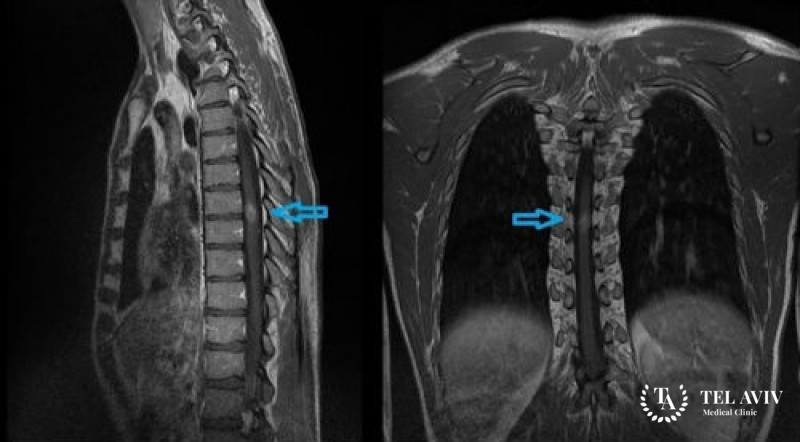

- Обычно оно включает в себя магнитно-резонансную томографию, как наиболее эффективный в данном случае источник информации. Четкая визуализация позволяет оценить, насколько затронуты пораженными клетками соседние ткани, выяснить размер и форму опухоли. Для большей детальности врач может использовать контрастное вещество, которое вводится внутрь пациенту. Это помогает идентифицировать измененную ткань.